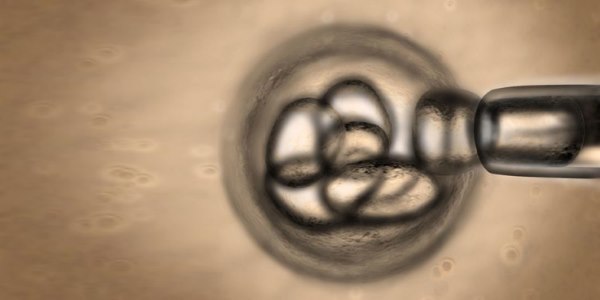

L’ipotesi classica sul sistema riproduttivo femminile vede la donna nascere con un numero finito di ovociti, che nel corso della vita riproduttiva si consumano fino a esaurimento, con il sopraggiungere della menopausa. Ma un gruppo di ricercatori del Vincent Centre for Reproductive Biology del Massachusetts General Hospital di Boston, Usa, guidati da Jonathan L. Tilly, confuta tutto ciò, dal momento che è riuscito a isolare cellule staminali ovariche da ovaie di donna e a produrre, a partire da queste, degli ovociti. Secondo Jonathan Tilly, questo significa che “in futuro potremmo arrivare al punto di avere addirittura una fonte illimitata di cellule uovo umane“.

Per essere sicuri che dalle cellule staminali vere e proprie sarebbero scaturite delle cellule uovo, gli autori della ricerca hanno marcato le staminali murine con una molecola fluorescente e le hanno iniettate in un frammento di tessuto delle ovaie umane. Passate 1 o 2 settimane, i ricercatori potevano così capire se le cellule staminali potevano produrle , osservando gli ovuli presenti sul tessuto fluorescenti. Questi risultati indicano che “le ovaie delle donne in età fertile contengono, come quelle dei topi adulti, delle rare cellule germinali mitoticamente attive che possono proliferare in vitro e produrre ovociti sia in vitro, sia in vivo“.